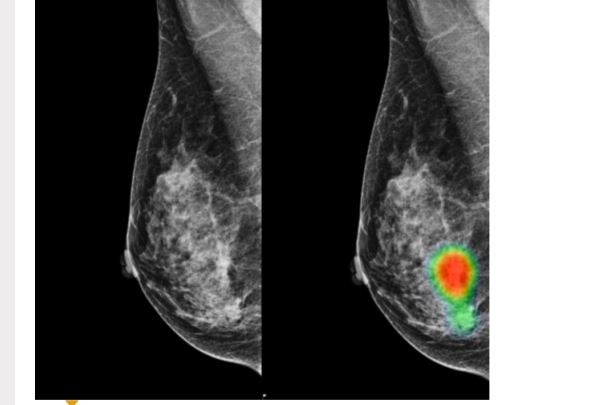

Mammografia jest   badaniem obrazowym, wykorzystującym niewielką dawkę promieniowania rentgenowskiego. Skupia się przede wszystkim na rozpoznaniu zmian w obrębie gruczołu piersiowego (sutka). Badanie mammograficzne polega na wykonaniu dwóch zdjęć rentgenowskich każdej piersi.